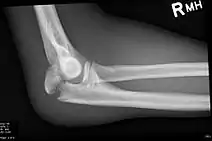

Olecranon fracture

Olecranon fracture is a fracture of the bony portion of the elbow. The injury is fairly common and often occurs following a fall or direct trauma to the elbow. The olecranon is the proximal extremity of the ulna which is articulated with the humerus bone and constitutes a part of the elbow articulation. Its location makes it vulnerable to direct trauma.

| Fracture of the olecranon | |

To assess an olecranon fracture, a careful skin exam is performed to ensure there is no open fracture. Then a complete neurological exam of the upper limb should be documented.[1][5] Frontal and lateral X-ray views of the elbow are typically done to investigate the possibility of an olecranon fracture.[2] A true lateral x-ray is essential to determine the fracture pattern, degree of displacement, comminution, and the degree of articular involvement.